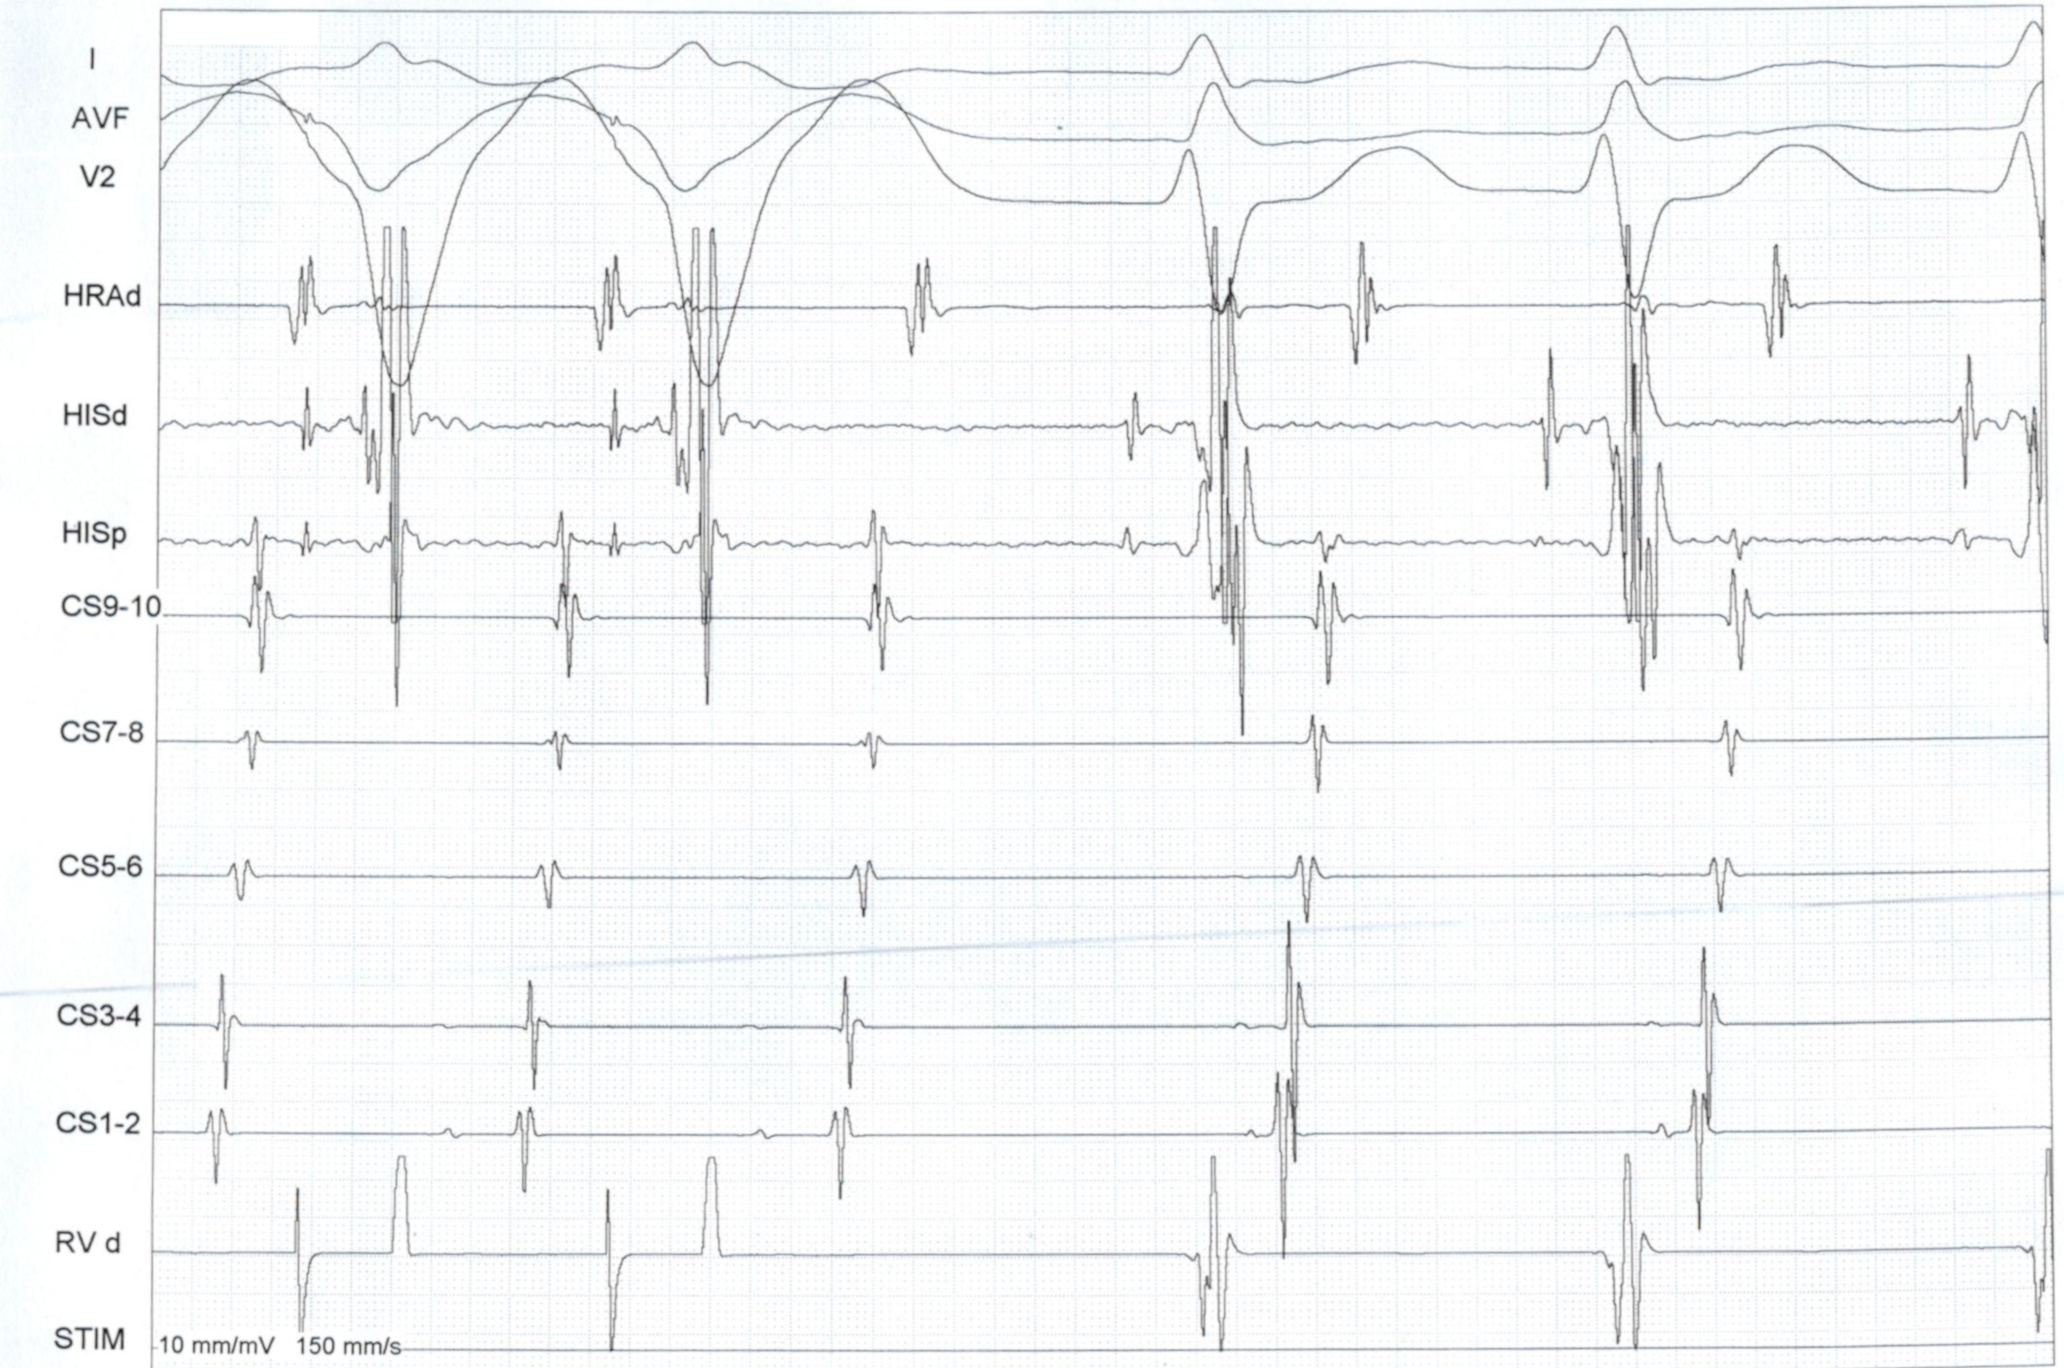

AVNRT vs AVRT

vav_measurements_ppi.jpg

SA / VA intervals

sa_va.jpg

• SA - VA and PPI - TCL are longer for AVNRT

• Can use basal pacing if responses are equivocal

• A entrained earlier for AVRT, entrained before His